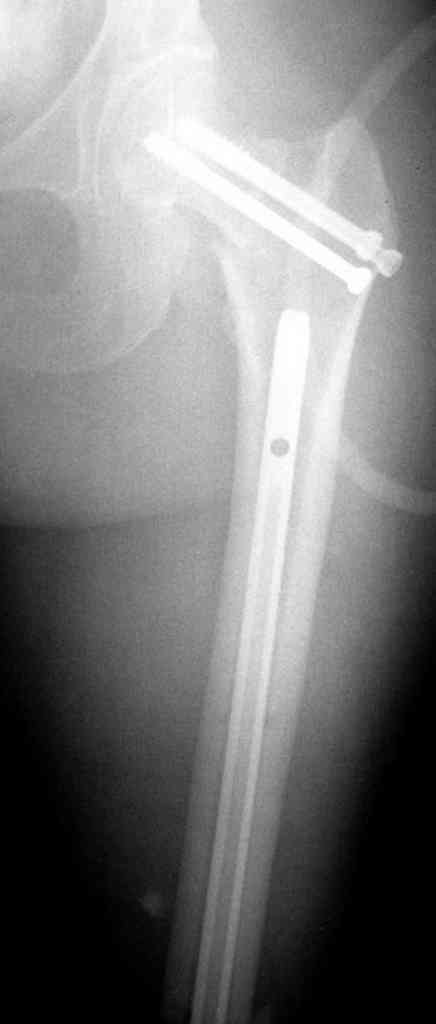

На снимках ложный сустав шейки бедра, несостоятельность фиксации. По положению шурупа можно предсказать ложный сустав, например, если screw backup за кортикальный слой около 15-20 мм, и также изменение угла от первоначального.

№2-3 типичная ошибка несоблюдения концепции параллельности шурупов, нарушение-фиксация поперечным допольнительным шурупом для приближения отломка в результате не сработало метод параллельных шурупов